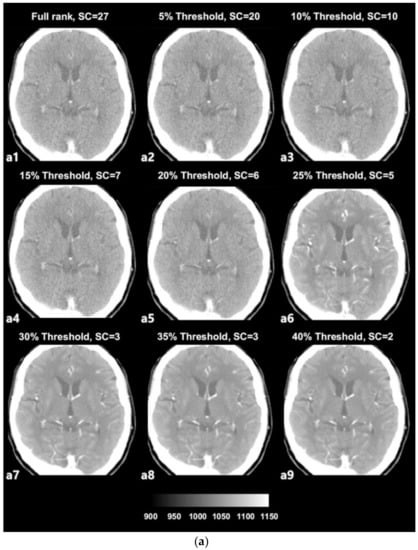

The SVD-based denoising technique was applied to 20 CTP datasets. Each dataset was reconstructed with singular values that were higher than the 5%, 10%, 15%, 20%, 25%, 30%, 35%, and 40% threshold values. Figure 3a depicts an example of denoised images corresponding to increasing thresholds. Figure 3b presents images with noise that were reconstructed with singular values lower than each threshold value and that were separated from the original full-rank image. In an example dataset, a full rank image (original noised Image) includes 27 singular value (Signal Component, SC) components. As shown in Figure 3a,b, the removal of larger amounts of Gaussian noise on an image is observed when the image is reconstructed with a smaller number of SCs (i.e., a larger number of low singular values were excluded).

(a) Example of denoised images based on thresholding values; a1—original image, a2–a9—denoised images. (b) Example of separated noise components in accordance with thresholding; b1—no noise component was separated from the original image, b2–b9—noise components separated from the original image corresponding to Figure 3.

The term ‘rank’ refers to the number of singular values added to reconstruct a single image [28,29]. The number of singular values in a rank was determined in relation to the threshold value. We selected the 2nd component of the diagonal S matrix as the threshold value on an experiential basis; there is no golden rule to guide the selection of the threshold value because the boundaries of the signal and noise components are still vague and unclear (Figure 2). Thresholding was the process used to approximately classify the singular values in terms of signal components and noise components. The singular values that were lower than the set threshold percentage value (2nd component) were assumed to be singular value noise components in every condition and were subsequently reconstructed into a noise-containing image (Figure 3b). In contrast, the singular values that were higher than the set threshold percentage value (2nd component) were assumed to be singular signal components in every condition and were subsequently reconstructed into a denoised image (Figure 3a).

In the used dataset, the full-rank image (original image, a1) included 27 SCs (Figure 3a), i.e., the 1st to the 27th components, which were in decreasing order of magnitude and were not yet classified. In the case of Figure 3a from a2 to a9, with increasing threshold percentages, larger numbers of components were classified as noise components, resulting in denoised images. For example, in the case of (Figure 3a, a2), the 1st to the 20th singular values were included to reconstruct the denoised image labeled as the 5% threshold image, and the 21st to the 27th singular values that were lower than 5% of the 2nd component were separated from the full-rank image and used to reconstruct the separated noise-containing image (Figure 3b, a9). The image a9 that is labeled as 40% of the threshold image was reconstructed including only the 1st and 2nd singular values by separating the largest number of SCs (25 SCs) from the full-rank image. Nonetheless, the image still appears to exhibit sufficiently high image quality. Regarding image a9, the 1st and 2nd singular values are predominantly depicted as providing diagnostic information. However, it is difficult to confirm that the image at the 40% threshold is the best one, as it simply involves the separation of a larger number of noise-related patterns; reducing the noise on a medical image is inevitably a trade-off for acquiring diagnostic information.